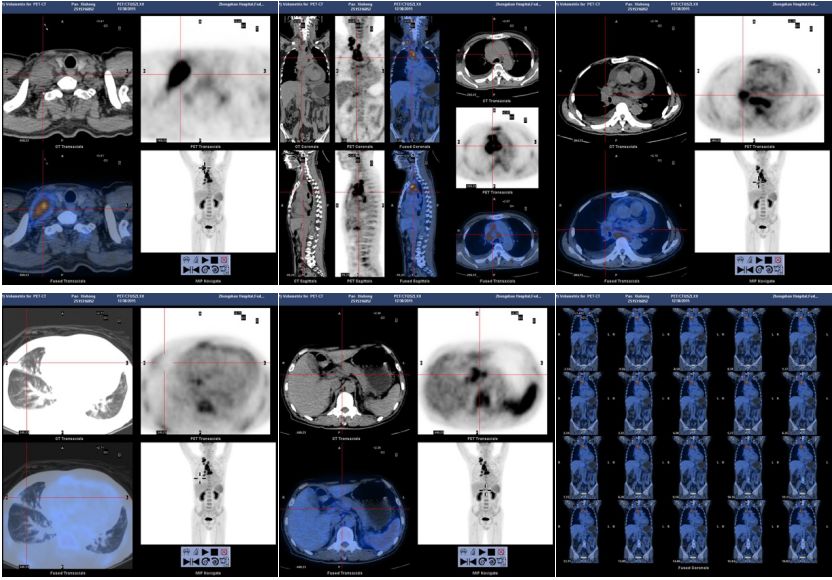

■ 辅助检查:WBC 10.95*109/L;CRP:126.9mg/L;ESR >120mm/H;D-二聚体1.53mg/L;自身抗体 抗核抗体:1:100,余阴性;细胞免疫功能:CD3 48.0%,CD4 22.0%,自然*伤杀**细胞(CD56+16) 33.0%。痰培养 (-);肺炎支原体弱阳性;T-SPOT:A孔0,B孔 0;EB病毒壳抗体IgM (+),巨细胞病毒IgG>500,风疹病毒IgG >500,G试验1-3-β-D葡聚糖 251.4。胸水常规:浑浊,蛋白定性(+),比重 1.034,红细胞 200/mm3,白细胞500/mm3,淋巴细胞95%,中性粒细胞5%;胸水生化:LDH 598 U/L,蛋白 47.16 g/L,葡萄糖 9.8mmol/L;胸水细菌、真菌培养(-)。PET/CT: 右侧锁骨区、胸内及肝胃间隙、肝门区、胰头周围糖代谢异常增高的肿大淋巴结双侧颈血管旁炎性淋巴结可能, 两肺慢性炎症, 双侧胸腔、心包腔积液, 全身骨髓、脾脏弥漫性糖代谢增高(图3,4)。

图3. 2015.12.30 PET-CT显示多发淋巴结肿大伴弥漫性代谢增高

图4. 2015.12.30 PET-CT显示双侧胸腔及心包腔积液